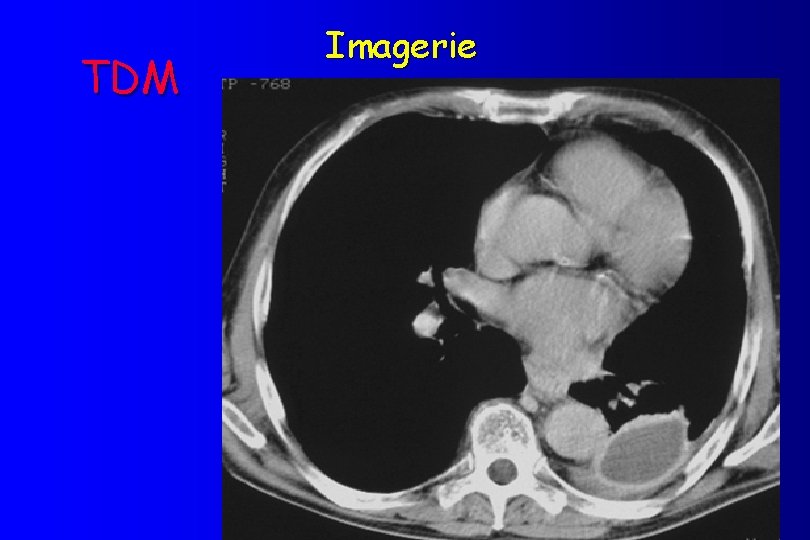

Pleurésies imagerie üRadios standard: opacité homogène, limite sup. concave, ligne bordande axillaire. üEchographie pleurale üTomodensitométrie (scanner) üScintigraphie pulmonaire üTomodensitométrie par Émission de positron (TEP)

TDM Imagerie